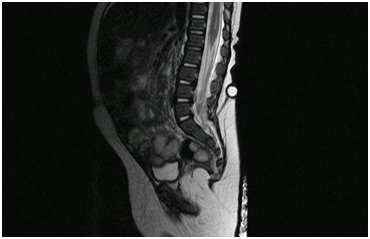

A 5-month-old infant that arrives to the pediatric emergency room (ER) with a chief complaint of fever of 12 hours (38ºC axillary), associated to vomits and irritability. A perinatological history of a pilonidal sinus within the center of a lumbosacral angioma detected at birth stands out, with an initial medullar ultra sonography that did not detect any communication. The rest of variables were within normal range. The physical exam revealed an angiomatous cutaneous lesion in the lumbosacral region L5-S1 with a pilonidal sinus and a hair follicle in the center of the lesion (Figure 1). Blood work showed WBC: 21300/mm3 (PMN 59%, Bands 3%, Lymphocytes 29%, Monocytes 9%), CRP: 143, 2mg/L and Procalcitonine: 2, 39ng/mL; VGB and the rest within the normal range. The CSF obtained was of purulent aspect, CSF cell count: WBC 8240/mm3 (PMN: 82%), CSF glucose: 0.18mg/dL, CSF protein: 0.86g/L, CSF gram stain: Gram negative bacillus, CSF culture grows an E. coli. Immunologic study without alterations. The patient was admitted and started treatment with cefotaxime (300 mg/kg/day),3 showing a clinical improvement within 6 hours of starting the treatment. The antibiotic was maintained for 22 days, with normalization of the CSF values by the end of the treatment.5 A new medullar ultrasound in the lumbosacral region was performed finding a hypoechoic tubular image starting form a hyperechoic subcutaneous nodular lesion in the sacral region that continues in depth into the sacral osseous elements. An MRI was then performed observing a fistula starting in the lumbosacral pilonidal sinus and continuing into the dura mater with a sacral osseous dysrafia (Figure 2). Within a month of discharge, and while waiting for the corrective neurosurgery, the patient presents with a new meningitis by E. coli, starting treatment again with cefotaxime (300mg/kg/day), receiving antibiotic treatment for 30 days in this second episode. A few days before ending the second course of antibiotics the surgical correction was successfully performed, with a resection of the cutaneomeningeal fistula and closure of the plains from skin to sacral meninges. Following the surgery, the infant has remained asymptomatic and has not presented any complications or new infections.

Figure 2 Medullar MRI. Cutaneomeningeal lumbosacral fistula.